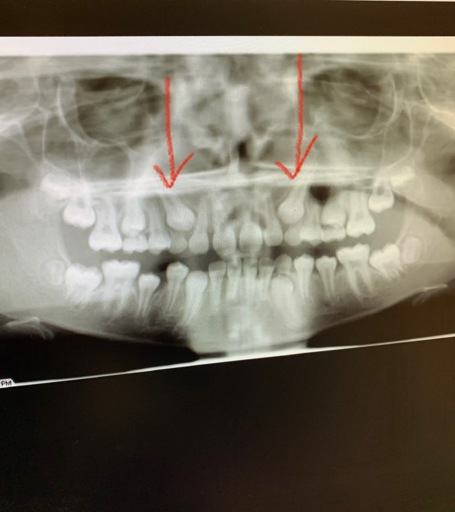

Why Am I Missing Roots on My Wisdom Teeth?

I'm having my wisdom teeth taken out soon. I was told that none of the four wisdom teeth have roots. I even saw the x rays, and it just looked like the top of a normal molar. They have not broken through the gums yet, but they felt I needed them out...